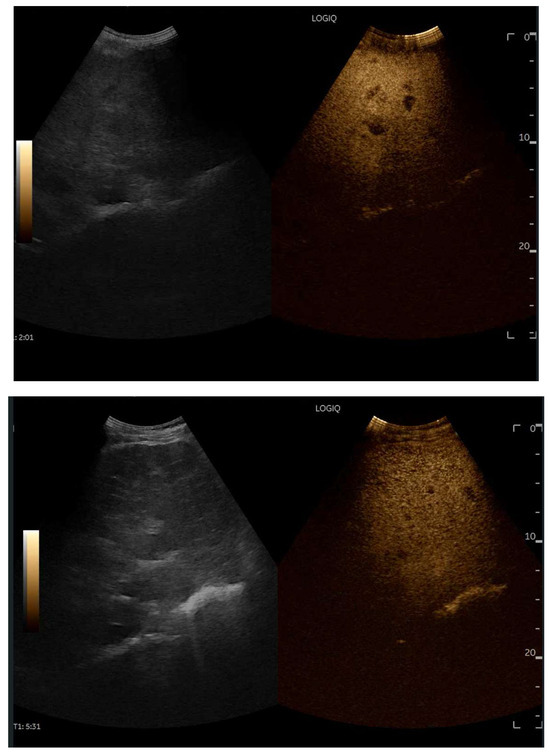

Abdominal ultrasound is a fundamental diagnostic tool in clinical practice, due to its availability, safety, and overall accuracy. This Special Issue will delve into the most recent technological and methodological innovations in abdominal ultrasound imaging, offering readers a comprehensive overview of advanced techniques, specific clinical indications, and solutions to emerging challenges. Among the various topics, it will cover the use of high-resolution probes, the integration of elastography for assessing liver fibrosis, and the application of contrast-enhanced ultrasound for identifying complex lesions. Strategies for training and professional development will also be examined to improve ultrasound performance and result interpretation.